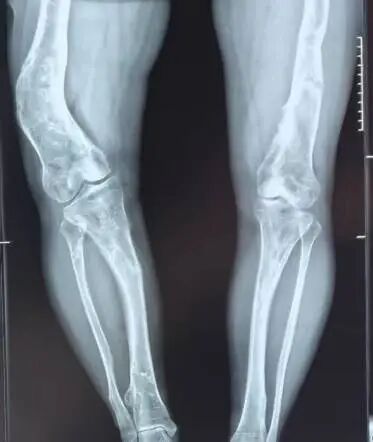

根据X光显示,她右侧股骨畸形突出,双下肢长度差肉眼可见。

患者术前X光片